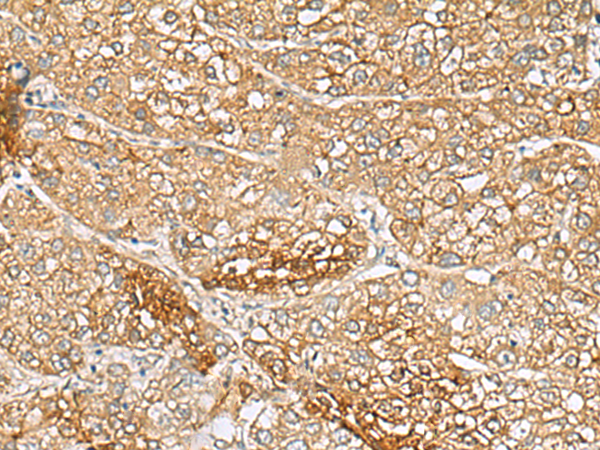

分类: 科研抗体货号: P09414别名: DECRD; MNADK; NADKD1; C5orf33应用: WB,IHC反应种属: Human, Rat